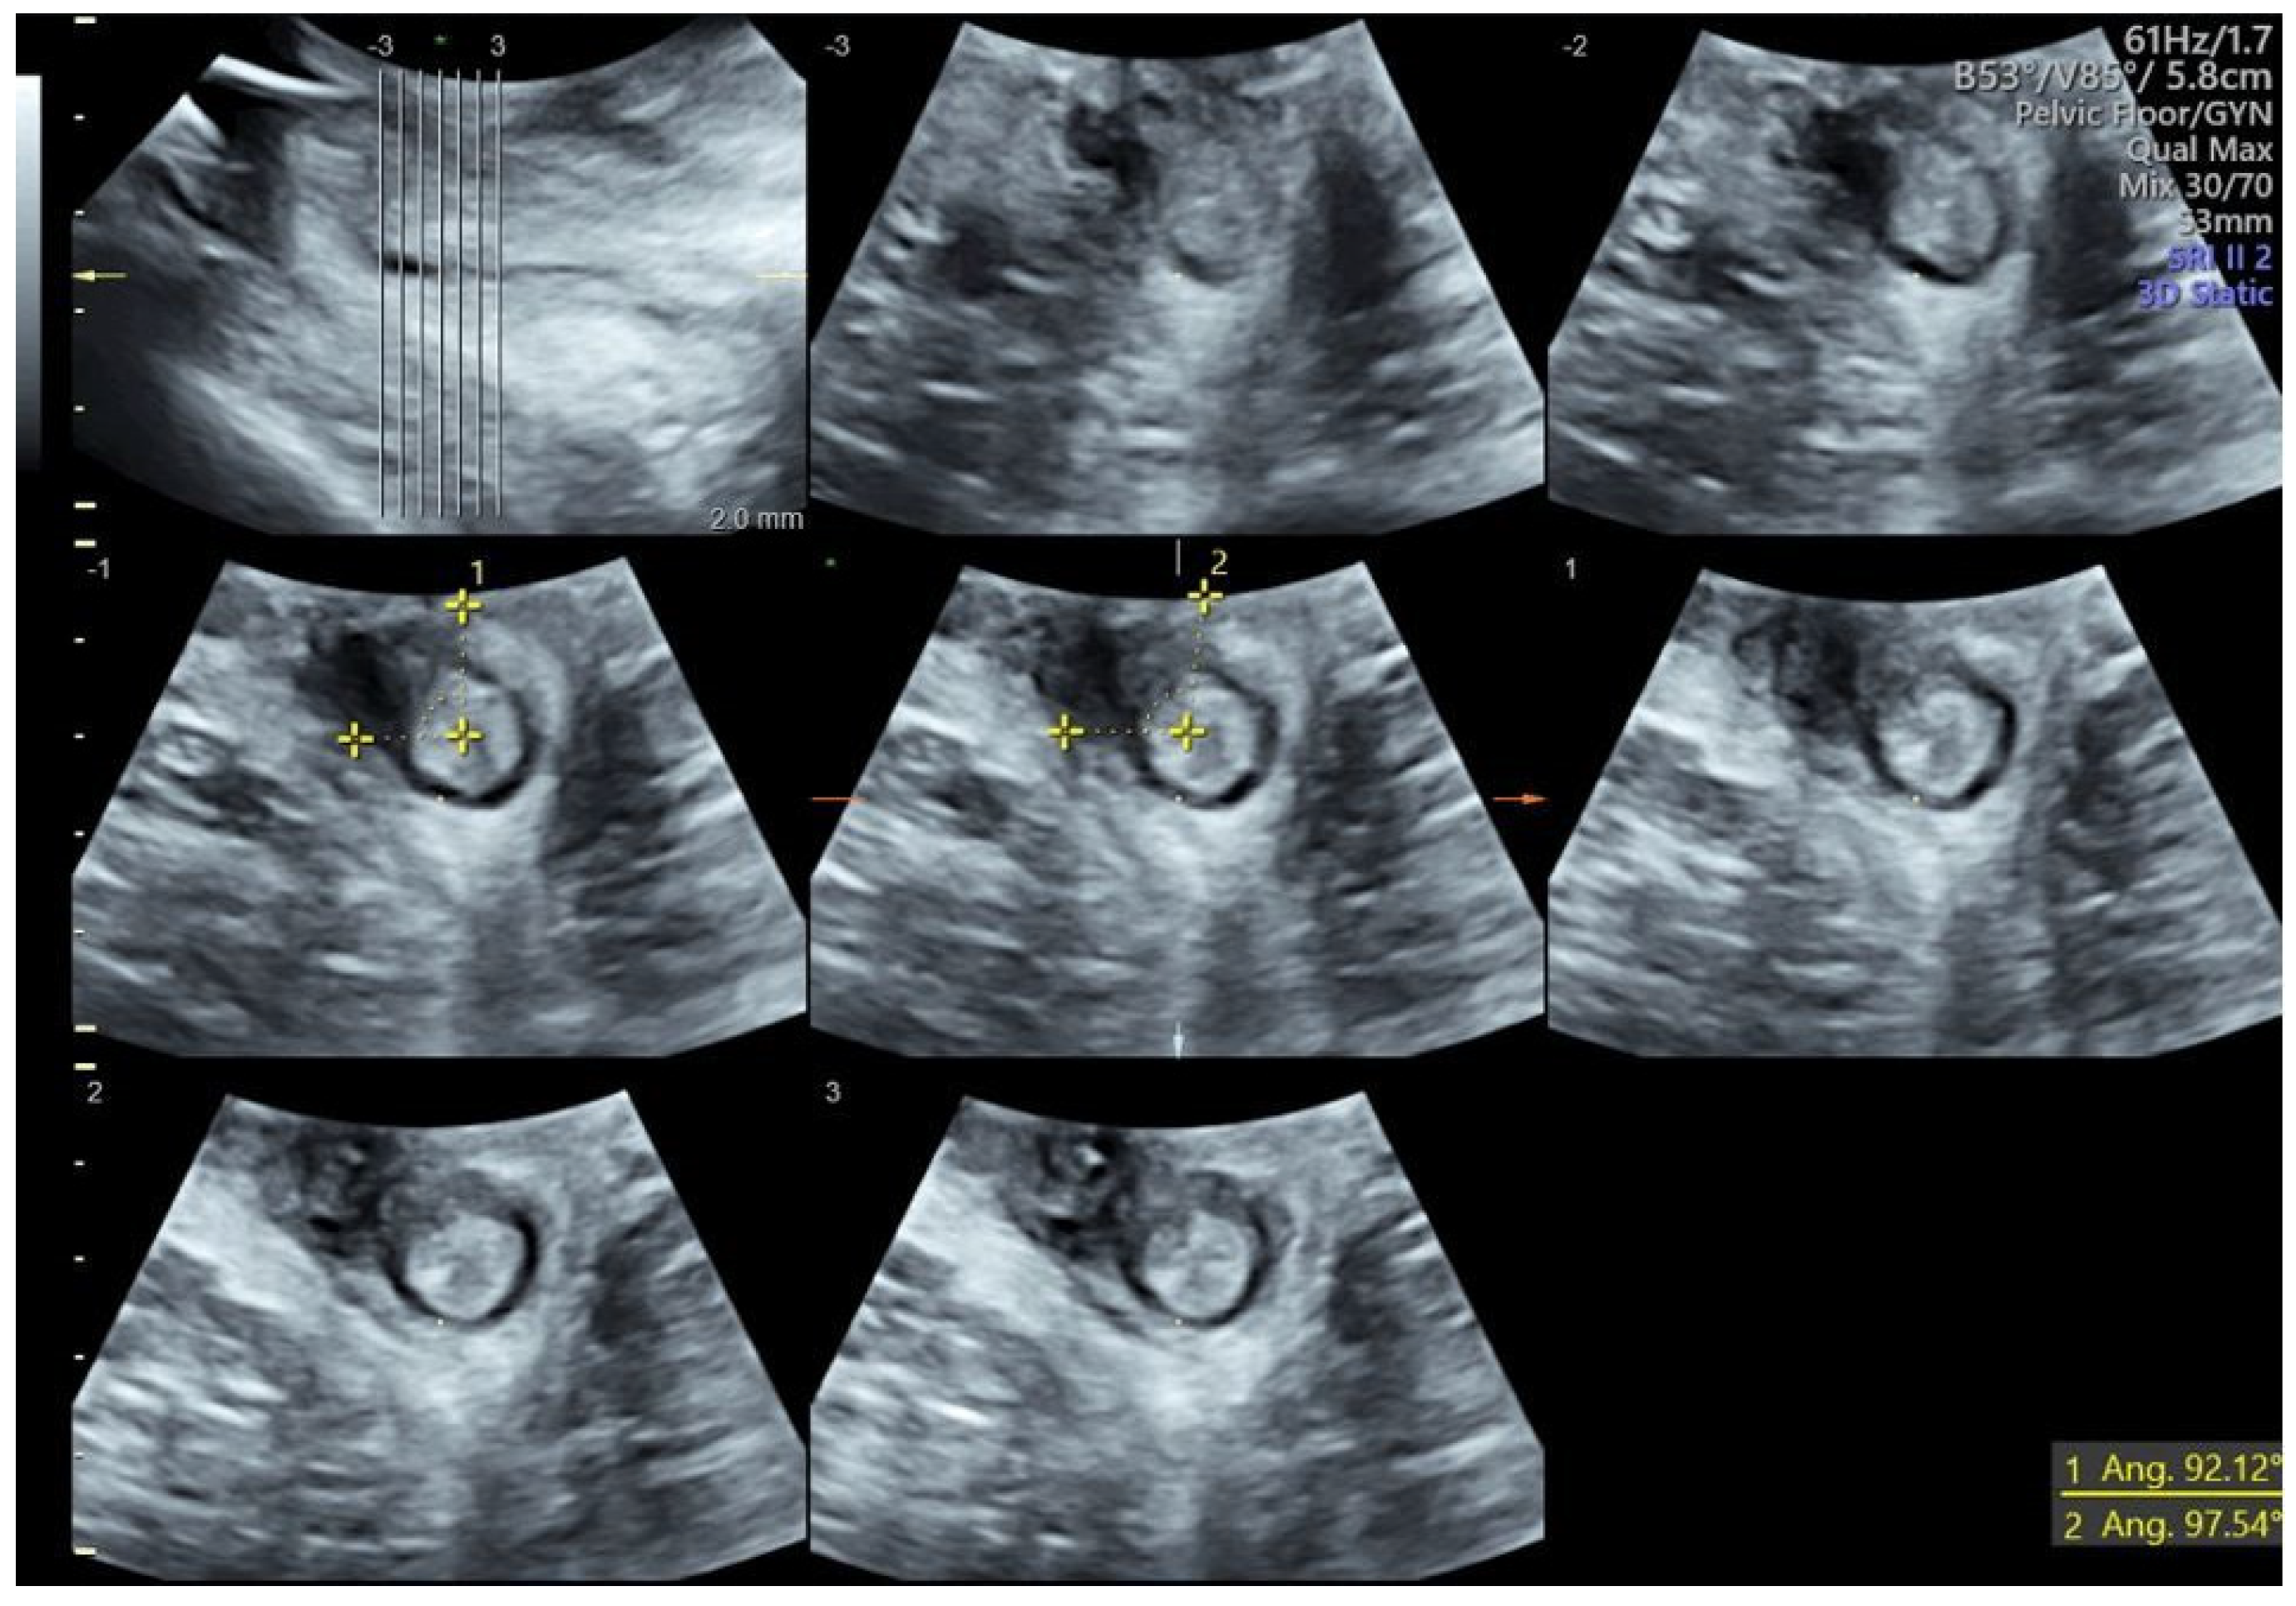

- Stickelmann, A.-L.; Kennes, L.N.; Hölscher, M.; Graef, C.; Kupec, T.; Wittenborn, J.; Stickeler, E.; Najjari, L. Obstetric Anal Sphincter Injuries (OASIS): Using Transperineal Ultrasound (TPUS) for Detecting, Visualizing and Monitoring the Healing Process. BMC Women’s Health 2022, 22, 339. [Google Scholar] [CrossRef] [PubMed]

- Ros, C.; Martínez-Franco, E.; Wozniak, M.M.; Cassado, J.; Santoro, G.A.; Elías, N.; López, M.; Palacio, M.; Wieczorek, A.P.; Espuña-Pons, M. Postpartum Two- and Three-Dimensional Ultrasound Evaluation of Anal Sphincter Complex in Women with Obstetric Anal Sphincter Injury. Ultrasound Obs. Gynecol. 2017, 49, 508–514. [Google Scholar] [CrossRef]

- Hakim, S.; Santoso, B.I.; Djusad, S.; Moegni, F.; Surya, R.; Kurniawan, A.P. Diagnostic Capabilities of Transperineal Ultrasound (TPUS) to Evaluate Anal Sphincter Defect Post Obstetric Anal Sphincter Injury (OASIS)? A Systematic Review. J. Ultrasound 2023, 26, 393–399. [Google Scholar] [CrossRef]

- Volløyhaug, I.; Taithongchai, A.; Arendsen, L.; Van Gruting, I.; Sultan, A.H.; Thakar, R. Is Endoanal, Introital or Transperineal Ultrasound Diagnosis of Sphincter Defects More Strongly Associated with Anal Incontinence? Int. Urogynecol. J. 2020, 31, 1471–1478. [Google Scholar] [CrossRef]

- Barbosa, M.; Christensen, P.; Møller-Bek, K.; Brogaard, L.; Glavind-Kristensen, M. Can Ultrasound 10 Days after Obstetric Anal Sphincter Injury Predict Anal Incontinence at Long-Term Follow-Up? Int. Urogynecol. J. 2021, 32, 2511–2520. [Google Scholar] [CrossRef]

- Abdool, Z.; Sultan, A.H.; Thakar, R. Ultrasound Imaging of the Anal Sphincter Complex: A Review. BJR 2012, 85, 865–875. [Google Scholar] [CrossRef]

- García-Mejido, J.A.; Gutiérrez Palomino, L.; Fernández Palacín, A.; Sainz-Bueno, J.A. Aplicabilidad de la ecografía transperineal en 3/4D para el diagnóstico de lesiones del esfínter anal durante el posparto inmediato [Applicability of 3/4D transperineal ultrasound for the diagnosis of anal sphincter injury during the immediate pospartum]. Cir. Cir. 2017, 85, 80–86. [Google Scholar] [CrossRef]